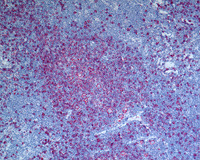

Figure 7; Areas with pattern E

Very little nodular pattern is appreciated here on the H&E slides. However, CD20 stain shows preserved nodularity with paucity of background small B-cells.